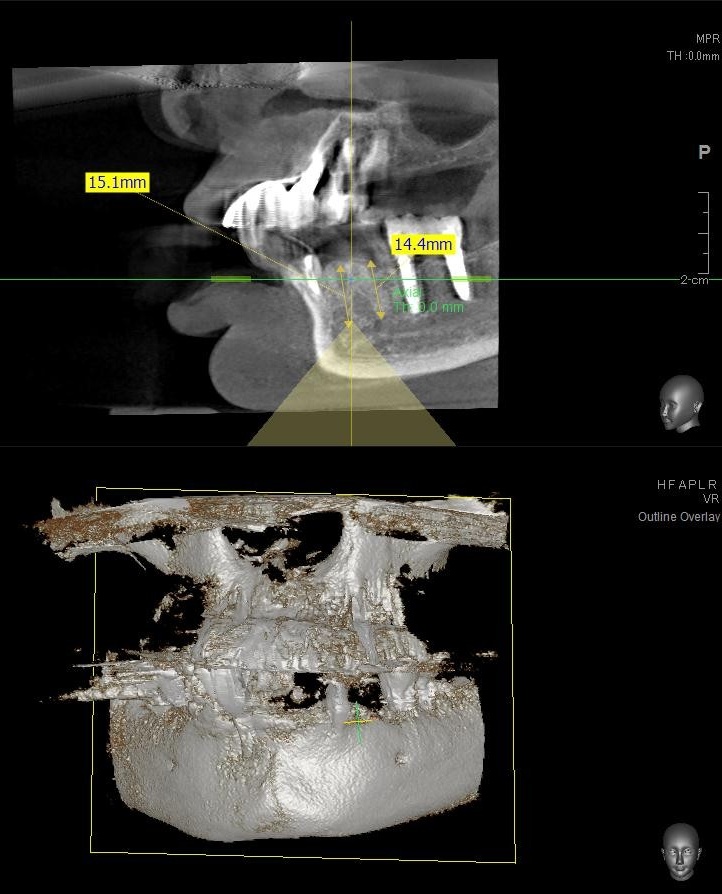

ドリルの先端を細い物から徐々に大きい物に変えながら、植立するインプラント体のネジの部分を除いた胴の部分の太さに合わせた大きさの穴を開けていきます。

開けた穴に、専用道具を使ってネジを締めるように長さ2センチ程のインプラントを骨に埋め込んでいきます。

しっかりとインプラント埋め込まれた後は、動揺がないか、噛んだ時に当たらないかなどを確認して、最後にパノラマ写真を撮影して今回のオペは終了となりました。